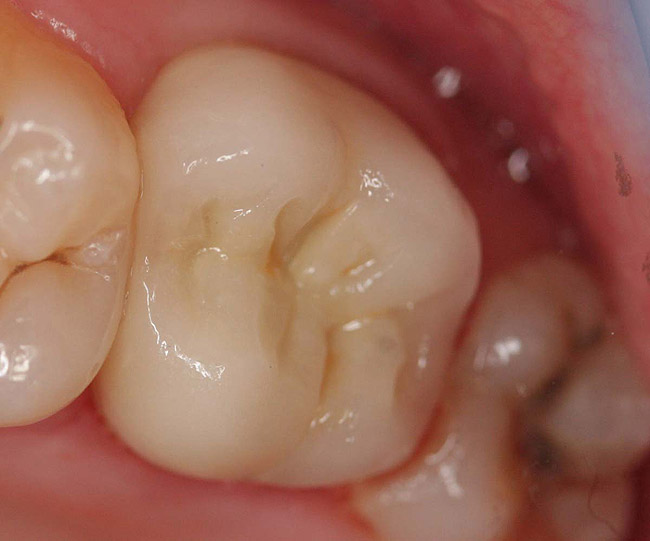

Case 2

A Class IIIN maxillary left second molar required restoration (Figure 6). Four canals, a chamber space, and little cross section of tooth structure were in the gingival third. Gutta-percha was removed with a Peeso reamer supplied in the C-1 kit. The canal was shaped with a bur in the kit, which was the same size as the corresponding post (Figure 7). The tooth structure was bonded with Brush & Bond™ (Parkell, www.parkell.com), and then the resin cement was spun into the canal with a lenticulo spiral. A C-1 white post was placed in the palatal canals (Figure 8). The C-1 White Post is a fiber-reinforced composite post, which flexes at the same rate as dentin to minimize root stresses.

Figure 6  Endodontically treated maxillary right second molar.

Figure 6